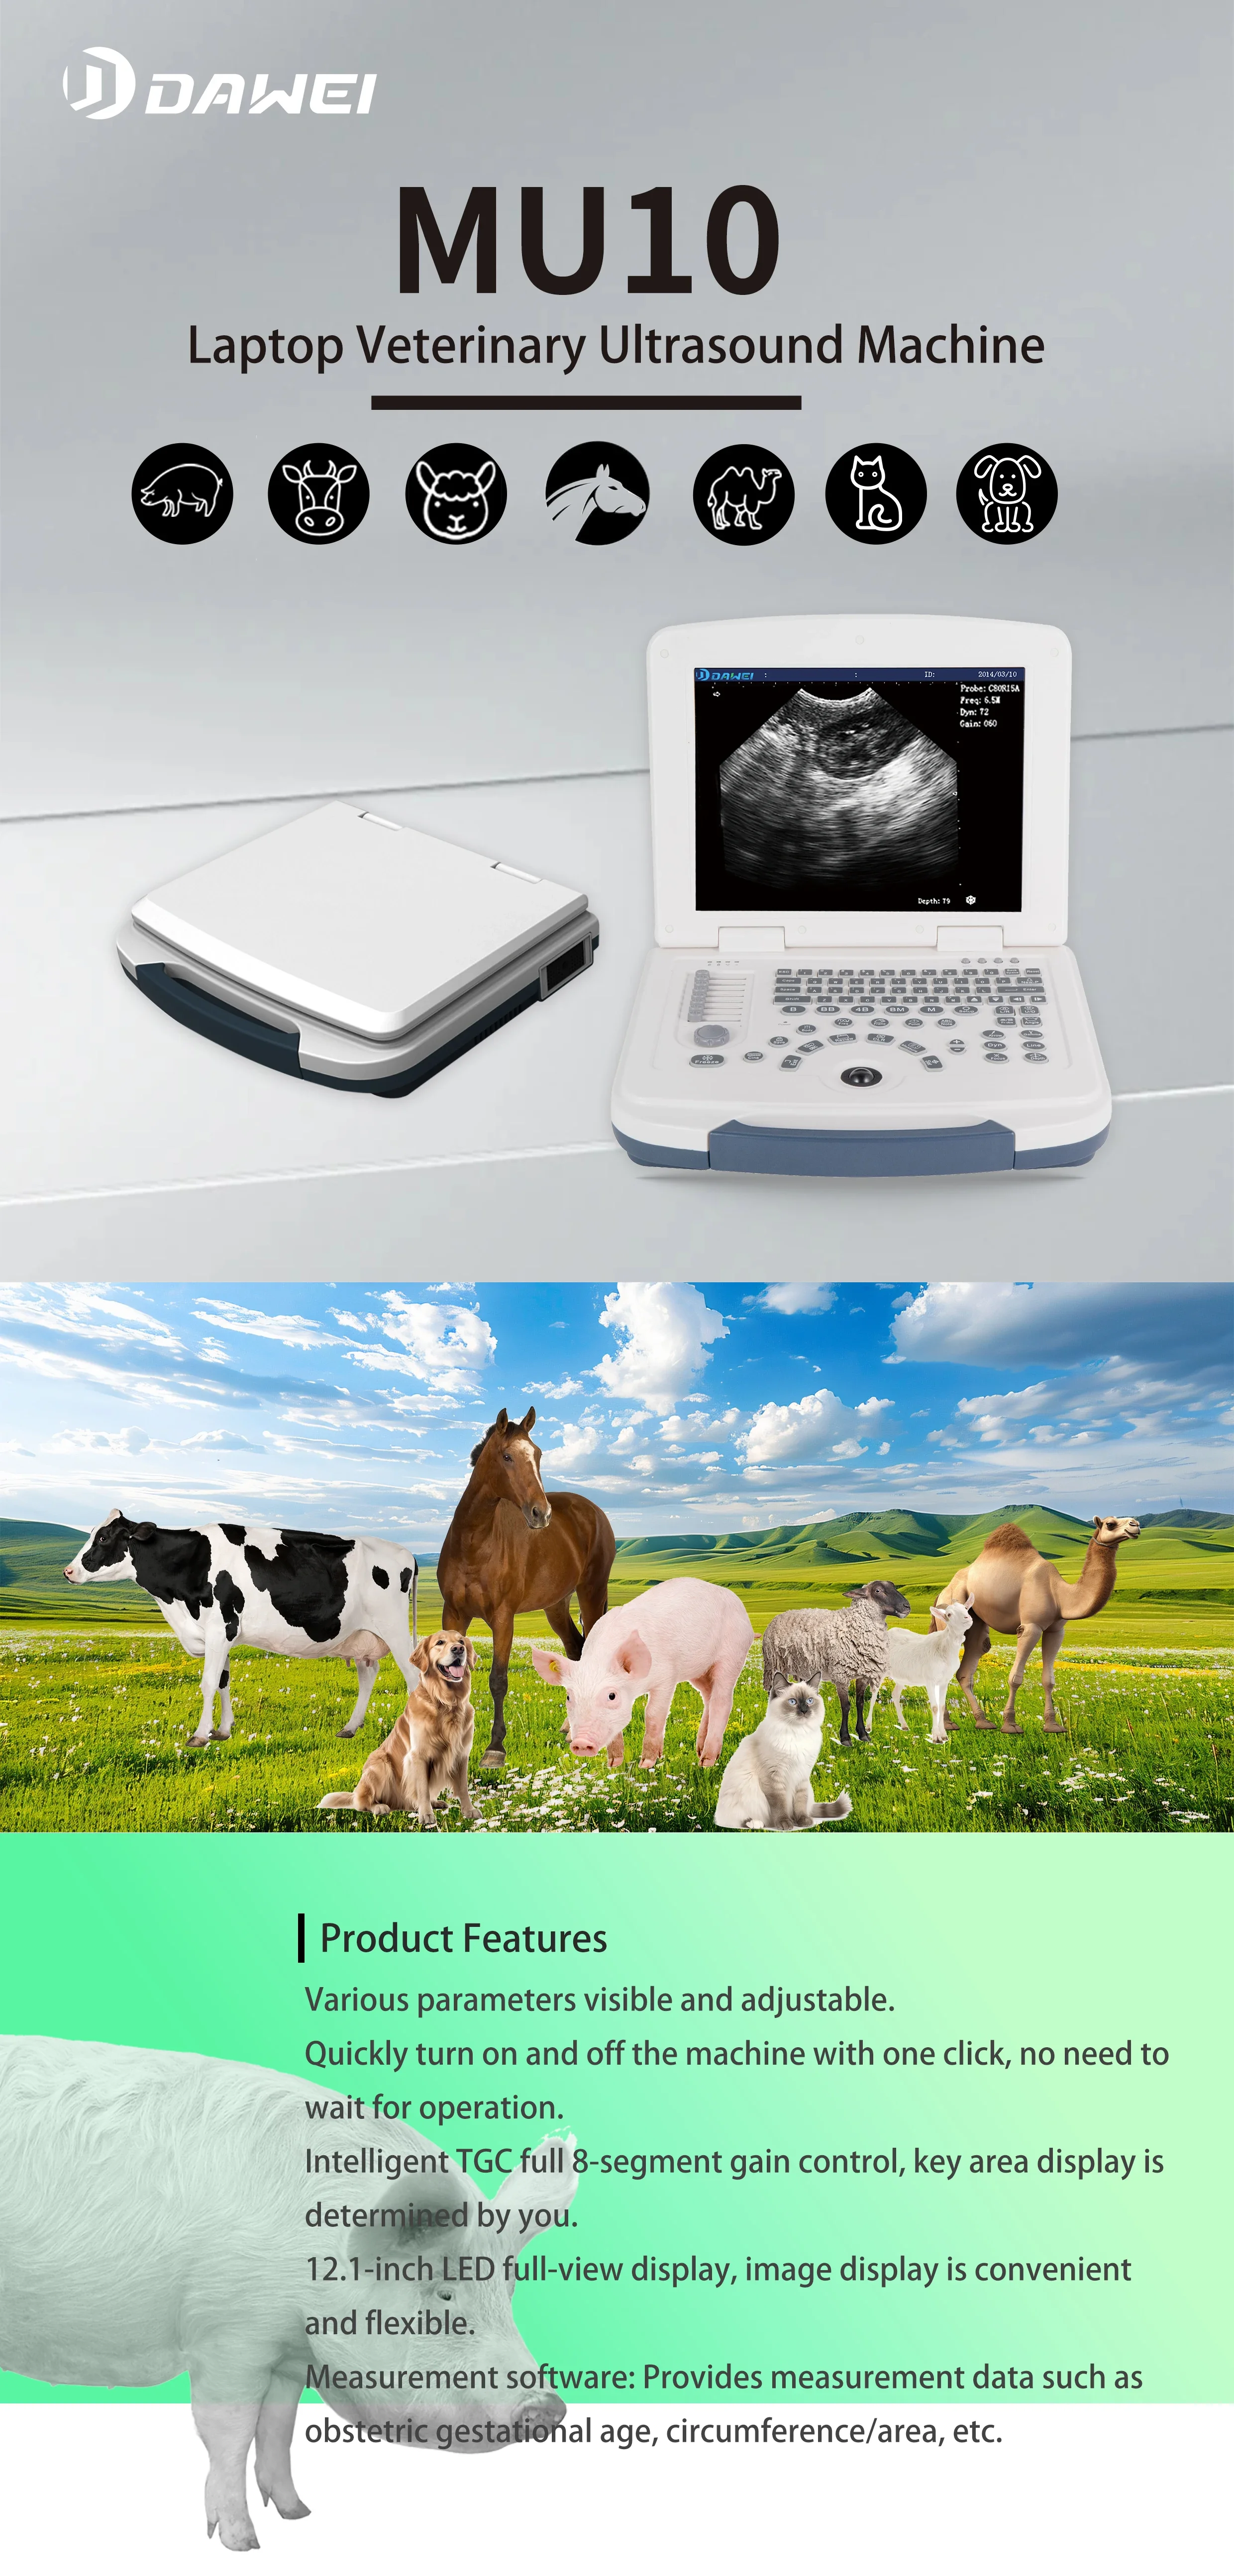

Small Full Digital Portable Ultrasound Equipment with Android/IOS Windows

Convex Probe Pictures:

This machine can be used for both humans and animals: